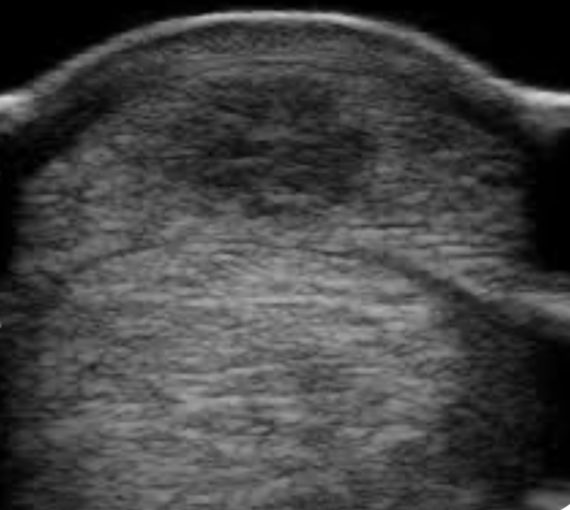

Rask diagnose er avgjørende ved øyeskader, noe som betyr at veterinærer må vurdere tilstanden før resepter utstedes. Ved øyebetennelse evaluerer vi hevelse, ødemer, vinkel til øyevipper, og tåreflod, blant annet, før hesten beroliges for en grundigere undersøkelse. Støtte for hodet kan være nyttig for en mer nøyaktig vurdering av øyet, spesielt ved svært smertefulle tilstander der lokalbedøvelse kan være nødvendig for en grundig utredning. Reflekser som pupillrefleks og truerefleks observeres, ofte ved hjelp av forskjellige fargingsmetoder. For eksempel, Fluorescein farger strukturer som Descemets membran, og evaluering av fargede områder gir innsikt i skadens dybde. Ultralyd er en effektiv metode for […]

De fleste avlshoppeiere er kjent med bruken av ultralyd for å vurdere eggstokker, livmor, livmorhals, og for å følge drektigheten fra anlegg til fosterblære og fosterets hjerteslag blir synlig. Sportshesteeiere blir også kjent med ultralyd ved undersøkelser av hevelser i bena. Ultralyd benyttes bredt for undersøkelser som involverer sener, senekjeder, ligamenter, og spesifikt collateralligamentene til hovleddet. Skader som gaffelbåndskader og vanlige skader i dype og overflatiske bøyesener samt støtteligamentet kan undersøkes nøye ved hjelp av ultralyd. Tidligere har danske veterinærer fra Hørsholm hestepraksis holdt vellykkede ultralydkurs for norske veterinærer om vurdering av leddnære strukturer. Ultralyd er også nyttig for å […]